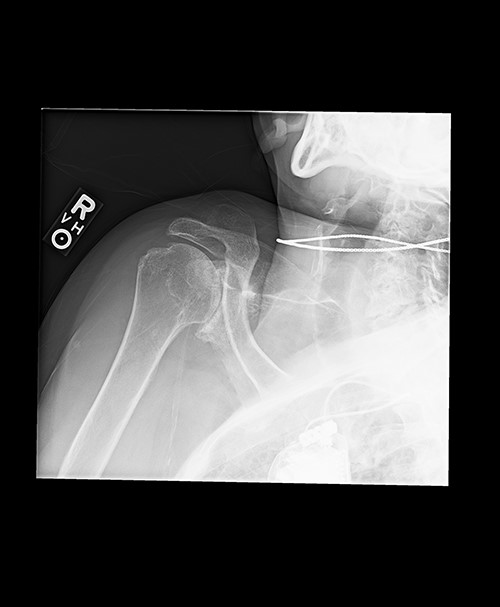

Radiologic imaging revealed bone-on-bone apposition of the glenohumeral joint, with superior humeral head migration consistent with rotator cuff tear arthropathy (Figs 1 and 2).

Grashey view demonstrating glenohumeral osteoarthritis with acromiohumeral space narrowing and superior humeral head migration.